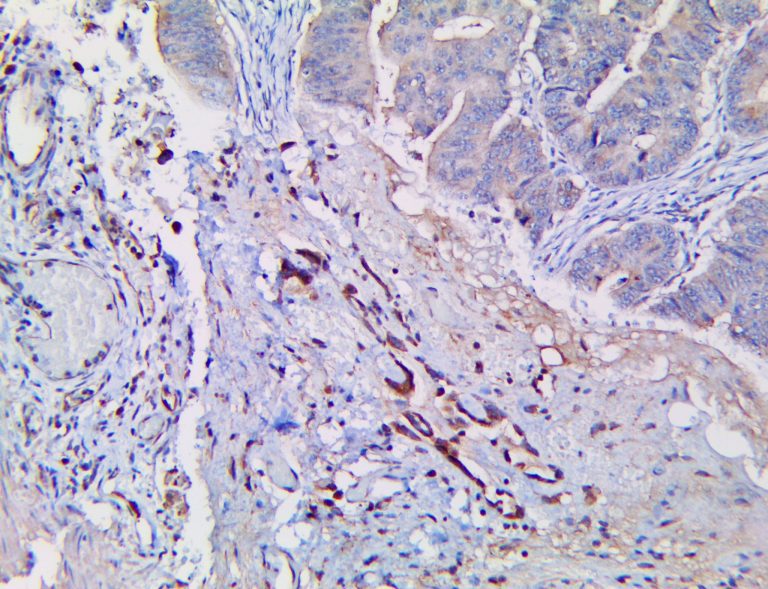

It is the ICU physician who is most likely to witness one of the deadliest manifestations of the abnormal immunological response, the cytokine storm syndrome (CSS). This response is also referred to by some as the cytokine release syndrome (CRS). CSS is characterized by continuous activation and expansion of macrophage and lymphocyte populations, which secrete large amounts of cytokines, causing the cytokine storm. This massive cytokine release is akin to hemophagocytic lymphohistiocytosis (HLH) disease, a syndrome characterized by initial unchecked and persistent activation of cytotoxic T lymphocytes and NK cells.

Clinical and laboratory manifestations of HLH include fever, enlarged liver and/or spleen, neurologic dysfunction, coagulopathy, liver dysfunction, cytopenias (i.e., low levels of erythrocytes, leukocytes, and/or platelets), hypertriglyceridemia, hyperferritinemia, hemophagocytosis, and eventually diminished NK cell activity as the immune system becomes progressively paralyzed. HLH can be familial (primary HLH) or secondary to another disease process (sHLH), such as rheumatic disease, in which it is referred to as macrophage activation syndrome (MAS, characterized by elevated ferritin).

This activation induces inflammatory monocytes to highly express IL-6, starting a localized and then systemic cascade effect that results in hyperproduction of IL-6, which accelerates the inflammatory process. Because IL-6 also increases vascular permeability, excessive levels cause blood vessels to become very leaky. This, along with clotting factors released from vascular endothelial cells, stimulates the coagulation cascade, resulting in microthrombosis (tiny clots), which leads to ischemia and tissue death of the kidney, intestines, heart, liver, brain and extremities.